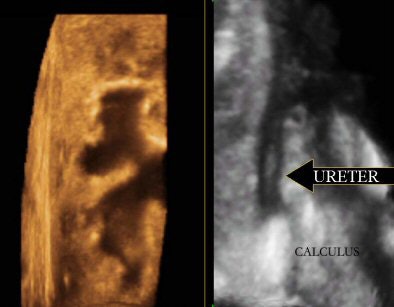

Fluid has always been the sonologist's friend, and 3D ultrasound has worked effectively in all fluid-filled structures. The virtual sonographic endoscopic views of the dilated calyceal systems and the urinary bladder have yielded spatial information about intraluminal lesions, their size, and their margins like never before. The presentation of information to the referring physician has also dramatically improved.

| Exquisite 3D reformation showing the dilated calcyceal system on the left and the dilated upper ureter with a calculus on the right. |